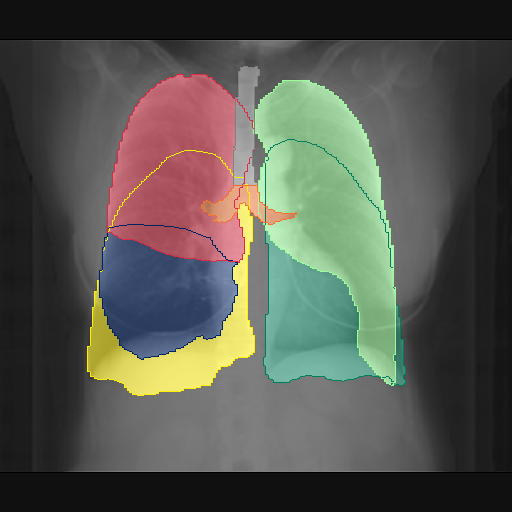

We show qualitative results for frontal projections in Fig. 2. We show a subset of classes belonging to the supercategories lungs, vascular systems, bones, and abdomen/digestive system. The predictions show minor deviations at the boundaries of the individual classes of the respiratory and vasculature system, while some inaccuracies become visible in the abdominal area. The qualitative results for the lateral projections are displayed in Fig. 2. Akin to the frontal view, the predictions show smoother borders but align with the ground truth. Apart from this, the segmentations provide matching insights on the thoracic anatomy with a slight deviation from the ground truth for both frontal and lateral views.

Fig. 2 shows quantitative segmentation results for frontal (top row) and lateral (bottom row) views. We display the class performances in the form of IoU (left), DICE (center), and Hausdorff distance (right) for each sample as a scatter plot with the mean performance for the classes shown by a line plot. Generally, we see performances for standard spinal classes, such as the thoracic vertebrae with average IoU-scores above 80%, while the average performance of rare vertebrae of the dataset belonging to the cervical and lumbar spine can drop down to 40%. In the frontal view, there exists more variance in thoracic vertebrae segmentation performance compared to the lateral view. Bone structures such as the sternum, clavicles, and scapula achieve IoUs in the mean from 85% to 95%. For ribs, we can see a noticeable performance drop for the anterior parts of the lower ribs independent of the side. The lower anterior ribs typically do not contain a large area, making them difficult to segment. This behavior is mirrored in the lateral view across the metrics. Abdominal classes can vary in segmentation quality as they occur in a nearly homogenous region. For example, while the liver or stomach are typically well-segmented, the duodenum and kidneys are more complex. Heart and Lung related classes show near-perfect segmentations with scores above 90% IoU. Breast tissue segmentation in comparison only achieves a mean of 70% mIoU. It can be noted that classes in the lateral view tend to have slightly better scores than their frontal counterparts.

We display qualitative results in Fig. 3. The annotators tend to be content with most annotations. There are edits at the extensions of the esophagus, trachea, and aorta and corrections of the lower ribs. There is little consensus for classes in the abdominal area, such as the stomach, as seen on the right of Fig. 3 . In contrast, the annotators often align for bone classes.

We show the quantitative segmentation performance against medical expert annotations for all classes in Fig. 3 . The dashed lines represent the IAA, whereas the dotted line displays the average MAA. As the task for the human annotators was not to annotate from scratch but to correct wrong pixel-wise predictions, we can see a high MAA for most classes. In the frontal view, the most significant disagreements exist for rare bone structures such as L3 and C4, lower ribs, the mediastinal distribution, or the breast tissue. The IAA and MAA are highly similar with mIoU of respective 95% and 94%. The Hausdorff distance for MAA is slightly lower than the IAA, indicating slight differences in boundary annotations while maintaining a considerable overlap with the other annotator. In the lateral view, the concrete delineation of rib structures appears ambiguous, leading to lower MAA and IAA with a greater IAA than MAA for all metrics in this supercategory. Overall there is less agreement between the medical experts in the lateral view, leading to a better average MAA than IAA across all metrics (i.e. 85% vs 83% mIoU). While the experts propose changes to the original predictions, they are often not overlapping. In the lateral view, rib segmentations can become quite hard to interpret. While both annotators disagree with the rib segmentations, they do not always agree on how they should look. Similarly to the frontal view, tube-like structures like the esophagus are extended as they can appear fractured at times.